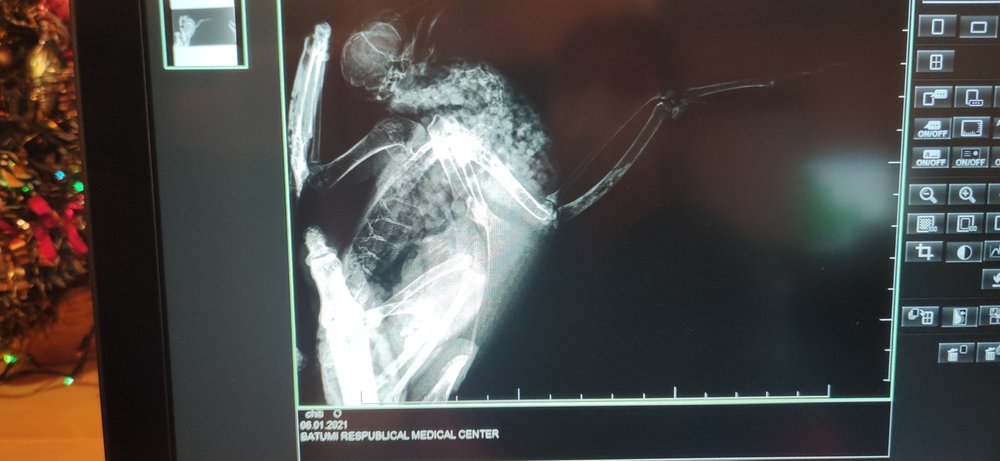

ksjsha Опубликовано 6 января, 2021 Автор #41 Опубликовано 6 января, 2021 (изменено) 42 минуты назад, ksjsha сказал: Ураааа,я такая реально счастливая?я договорилась за рентген в поликлинике,в ветклинике рентгена нету ? сейчас бегу за Гулей.Скажите,как именно мне его нужно делать и как Гулю дожить!? Я не уверена,что они знают?они же по людям. Вот так ,как на фото? Всех с рождеством! Я все сделала?не знаю радоваться или огорчаться?они говорят,что перелома нет. Я вот думаю,может я неправильно ее положила. Может плохо видно все ее косточки и суставы!? Что тогда с ней!?Ушиб что ли? Вот я высылаю вам снимки рентгена,что вы скажете!?Я ее положила на рентген, как на картинке сверху Изменено 6 января, 2021 пользователем ksjsha

ksjsha Опубликовано 6 января, 2021 Автор #43 Опубликовано 6 января, 2021 2 минуты назад, Beregovushka сказал: @ksjsha Вот тут внизу страницы посмотрите, как ястреб разложен в двух проекциях - на спине и на боку. https://www.mybirds.ru/health/rentgen.php Настройка аппарата должна быть как на кисть детской руки. Спасибо,но я уже сделала?не дождалась ответа. Мне кажется,что в этой части у нее проблема ,эта часть у нее висит. Или там все хорошо? Я почему- то уверена,что у нее оно сломанно и я ее неправильно как-то положила,что на снимке не видно ?

OFA Опубликовано 6 января, 2021 #44 Опубликовано 6 января, 2021 @ksjsha нужно Зосю, нашего доктора, звать в тему. Может она что-то увидит, она опытный доктор. По такому снимку плечевая засвечена, перелома вроде не видно, а вот сустав в каком состоянии, не знаю

маленький принц Опубликовано 6 января, 2021 #45 Опубликовано 6 января, 2021 @ksjsha поскольку форум пережимает фото обрежьте пожалуйста фотографии в электронной форме снимков рентгена нету? 2 часа назад, ksjsha сказал: Мне кажется,что в этой части у нее проблема ,эта часть у нее висит. надо было сделать снимок положив птицу на спину ВНИМАНИЕ за три часа до рентгена НЕ кормить и НЕ поить чтобы при переворачивании на спину не могла захлебнуться содержимым зоба постарайтесь получить рентген в электронной форме